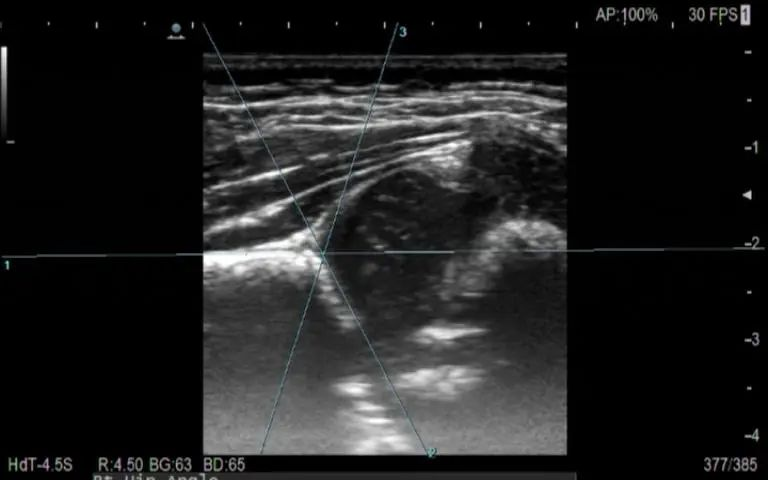

圖一:膝關(guān)節(jié)半月板損傷

圖二:腕管綜合癥